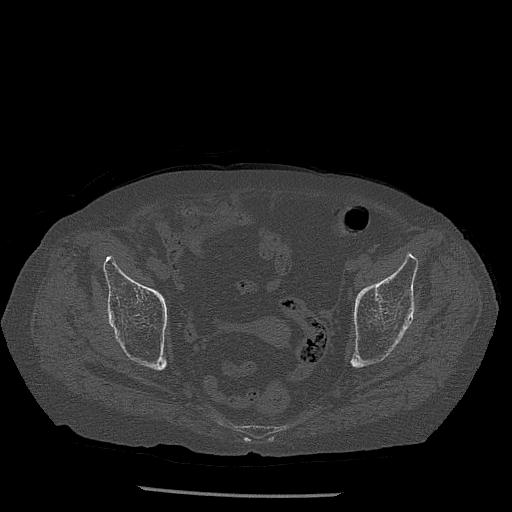

100703 1/27 両股正面+軸 1/29 両股正面+軸 94歳女性 パンソンロン